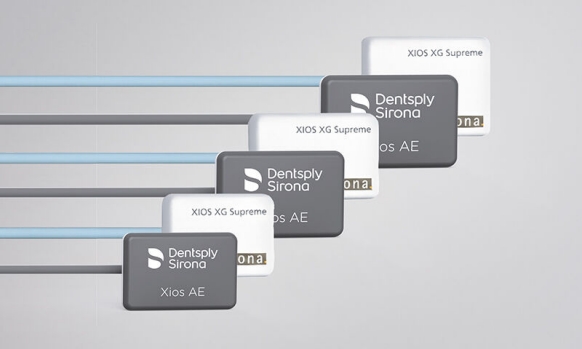

Imágenes superiores para cuidado óptimo del paciente

Los sensores intraorales de Dentsply Sirona proporcionan calidad de imagen de vanguardia que apoya el diagnóstico preciso del tratamiento y visión clara de la situación clínica. Respaldado por elecciones expansivas del sistema, mejora de filtro de imagen y servicio de vanguardia y personal de apoyo, los sensores intraorales Xios ofrecen varias posibilidades para su consultorio - brindándole beneficio a usted y sus pacientes.